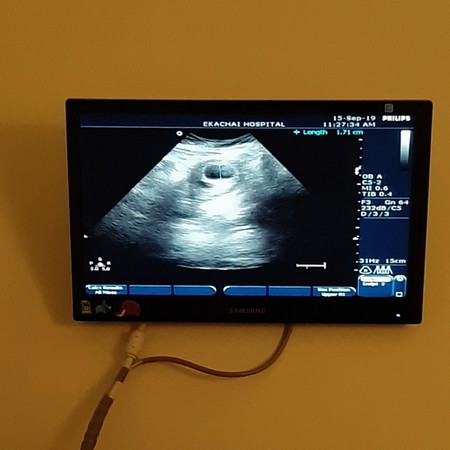

ท้องครั้งแรก...น้องอยู่ได้ไม่ถึง3เดือน ก็หลุด คุณหมอแจ้งว่า"เป็นภาวะแท้งคุกคาม"!! หลังจากนั้นไม่ถึงปี ก็มีน้องอีกครั้ง ท้องที่2 ดูแลน้องเป็นอย่างดี น้องออกมาแข็งแรงดี ตอนนี้โตเป็นหนุ่ม อายุได้ 7 ขวบ ผ่านไป 7ปี ตั้งใจมีน้องอีกครั้ง ท้องที่3 น้องอยู่ได้ประมาณ2เดือน ก็หลุดอีก คุณหมอแจ้งว่า "การฝังตัวของเซลล์ไม่สมบูรณ์ เลยทำให้น้องหลุดไป(แต่การที่แท้งทั้ง2ครั้ง ถือว่าโชคดีมาก เพราะเป็นการแท้งโดยสมบูรณ์ จึงไม่ต้องขูดมดลูก) ช่วงนั้นเสียใจมาก เพราะเราอยากจะมีเค้าจริงๆ พอตั้งหลักได้ ทั้งสามีและเราก็บำรุงกันเต็มที่ เพื่อจะมีน้องอีกครั้ง ในที่สุดน้องก็มาอีกครั้ง ซึ่งเป็นท้องที่ 4 ท้องนี้ น้องออกมาแข็งแรงดี ตอนนี้ อายุได้1ขวบนิดๆ แล้วก็มีข่าวดีอีกครั้ง ท้องที่5 ตอนนี้อายุครรภ์ประมาณ7week แต่เมื่อตอน 6week ไปซาวด์ดูน้อง เจอแต่ถุงน้ำคร่ำ ยังไม่เห็นตัวน้อง ตอนนี้มีความกังวลมาก กลัวจะท้องลม แต่คุณหมอบอกว่า "อย่าคิดมาก น้องยังเล็ก อวัยวะภายในแม่อาจจะบังอยู่ ไว้อีกรอประมาณ 8 week มาซาวด์ดูใหม่" เราก็ได้แต่ภาวนาให้ไปตรวจครั้งหน้าจะเจอน้อง? ผิดหวังมาเหนื่อยแล้วจริงๆ?